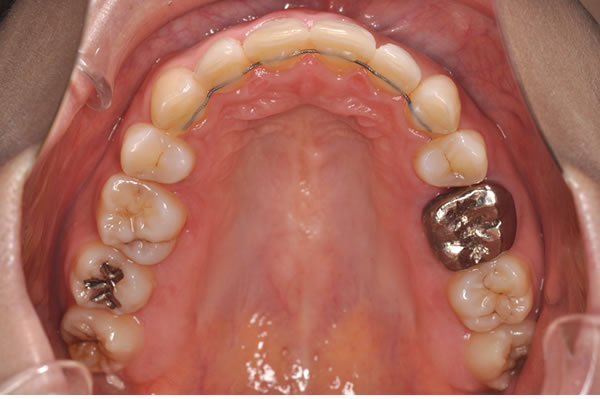

上顎前突症の治療例

上顎前突症(出っ歯)の矯正症例 ケース01

上顎前突症(出っ歯)の矯正症例 ケース02